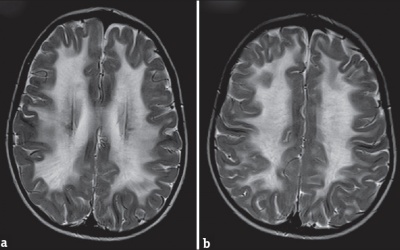

Thoái hóa chất trắng ở não thường xảy ra ở người cao tuổi, tuy nhiên, tình trạng này có thể xảy ra sớm ở người nghiện thuốc lá.